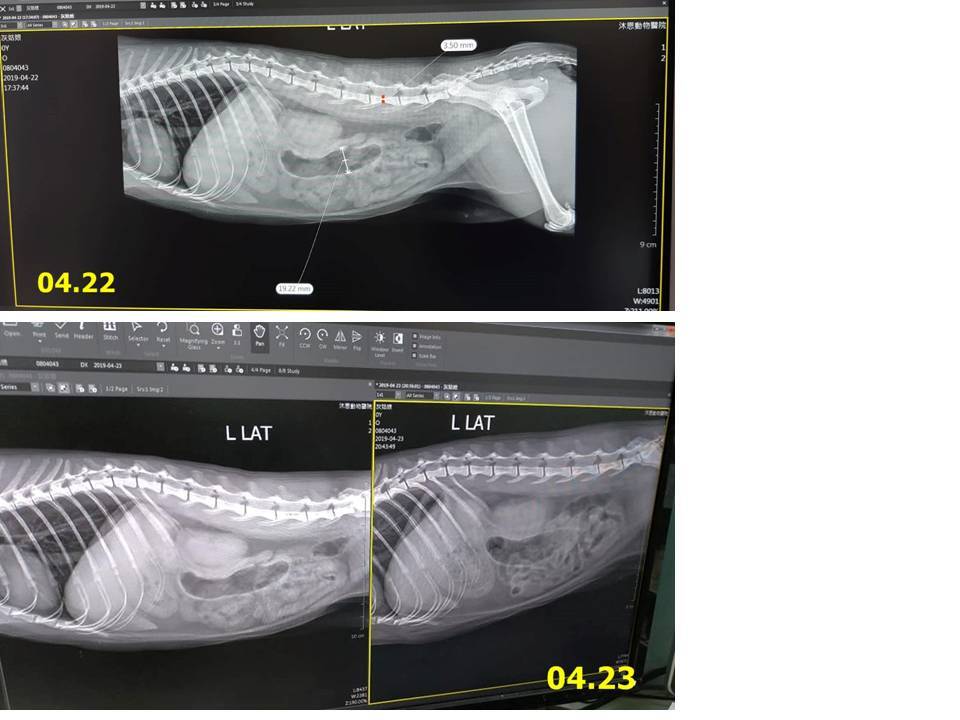

4月22日灰姑娘突然頻繁嘔吐,約診沐恩醫院檢查,血檢無發現異常,並無胰臟炎,X光檢查腸道空氣較多,有輕微脫水現象,因此醫師先為她打皮下輸液,並開藥帶回服用,但翌日灰姑娘又吐得厲害,工作人員趕緊再帶她就醫,超音波檢查與前一日的X光對照,懷疑有吃入異物,且多處淋巴結表示腸胃嚴重發炎,醫師調整用藥改為針劑治療,照護員依照指示幫灰姑娘打針並詳細觀察,一週的回診,灰姑娘嘔吐情況已改善很多,再開新藥吃完即可停。

1. X光片跟昨天對照,腸子內的空氣位置跟昨天一樣,沒有移動,懷疑是異物。

2. 掃超音波發現腸跟胃的蠕動是正常的,不過發現腸道內有多處淋巴結,表示腸胃嚴重發炎。